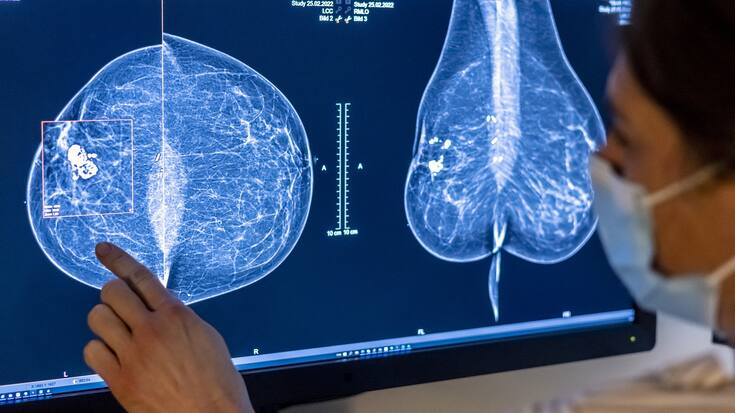

En 2022, les maladies non transmissibles telles que le cancer ont engendré des coûts de 65,7 milliards de francs: examen des seins d'une femme à la recherche d'un cancer du sein par mammographie. Keystone